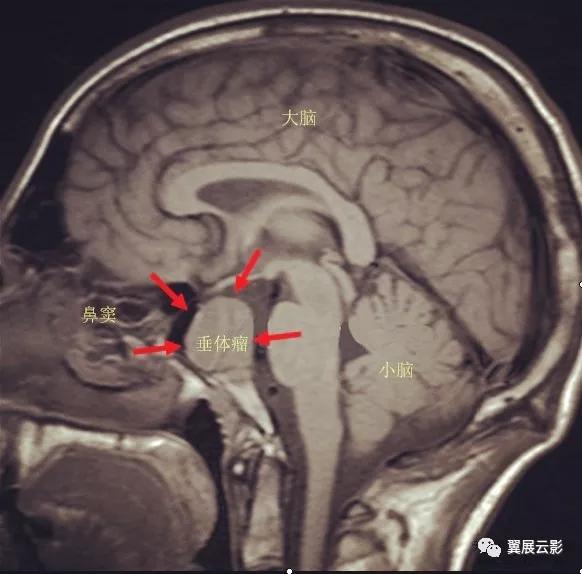

病例1:垂体大腺瘤

垂体大腺瘤多呈现卵圆形,葫芦状或雪人状,少部分侵袭性垂体瘤呈现不规则形或分叶状,MR扫描T1WI呈现长T1或等T1信号,T2WI呈现长T2或等T2信号,Gd-DTPA增强扫描肿瘤实质部分均匀强化,出血,囊变坏死区不强化,此外,尚可见蝶鞍扩大,鞍底下陷,视交叉上抬受压及海绵窦受累等征象。垂体微腺瘤MR平扫多呈现小结节状长T1长T2信号,病变局部垂体上缘膨隆,垂体柄向对侧移位,局部鞍底下陷或骨质破坏,动态增强早期微腺瘤强化不明显,而正常垂体组织强化明显,故增强早期微腺瘤呈现充盈缺损样改变,延迟期可出现轻中度强化,垂体大腺瘤重点描述肿瘤的形态,信号,蝶鞍的改变,海绵窦及视交叉受累情况。此外,还应注意瘤体内部是否合并出血,坏死囊变等改变。诊断时应注意与鞍上肿瘤如颅咽管瘤等相鉴别。